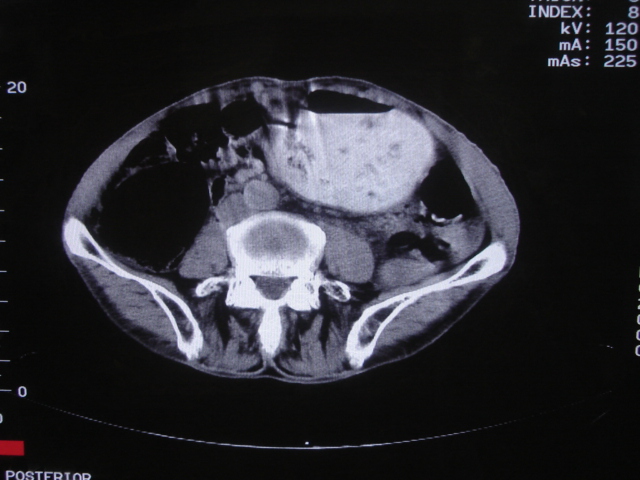

以下是引用深泽交通医院在2008-7-17 12:39:00的发言:[br]胃下垂;胃窦占位